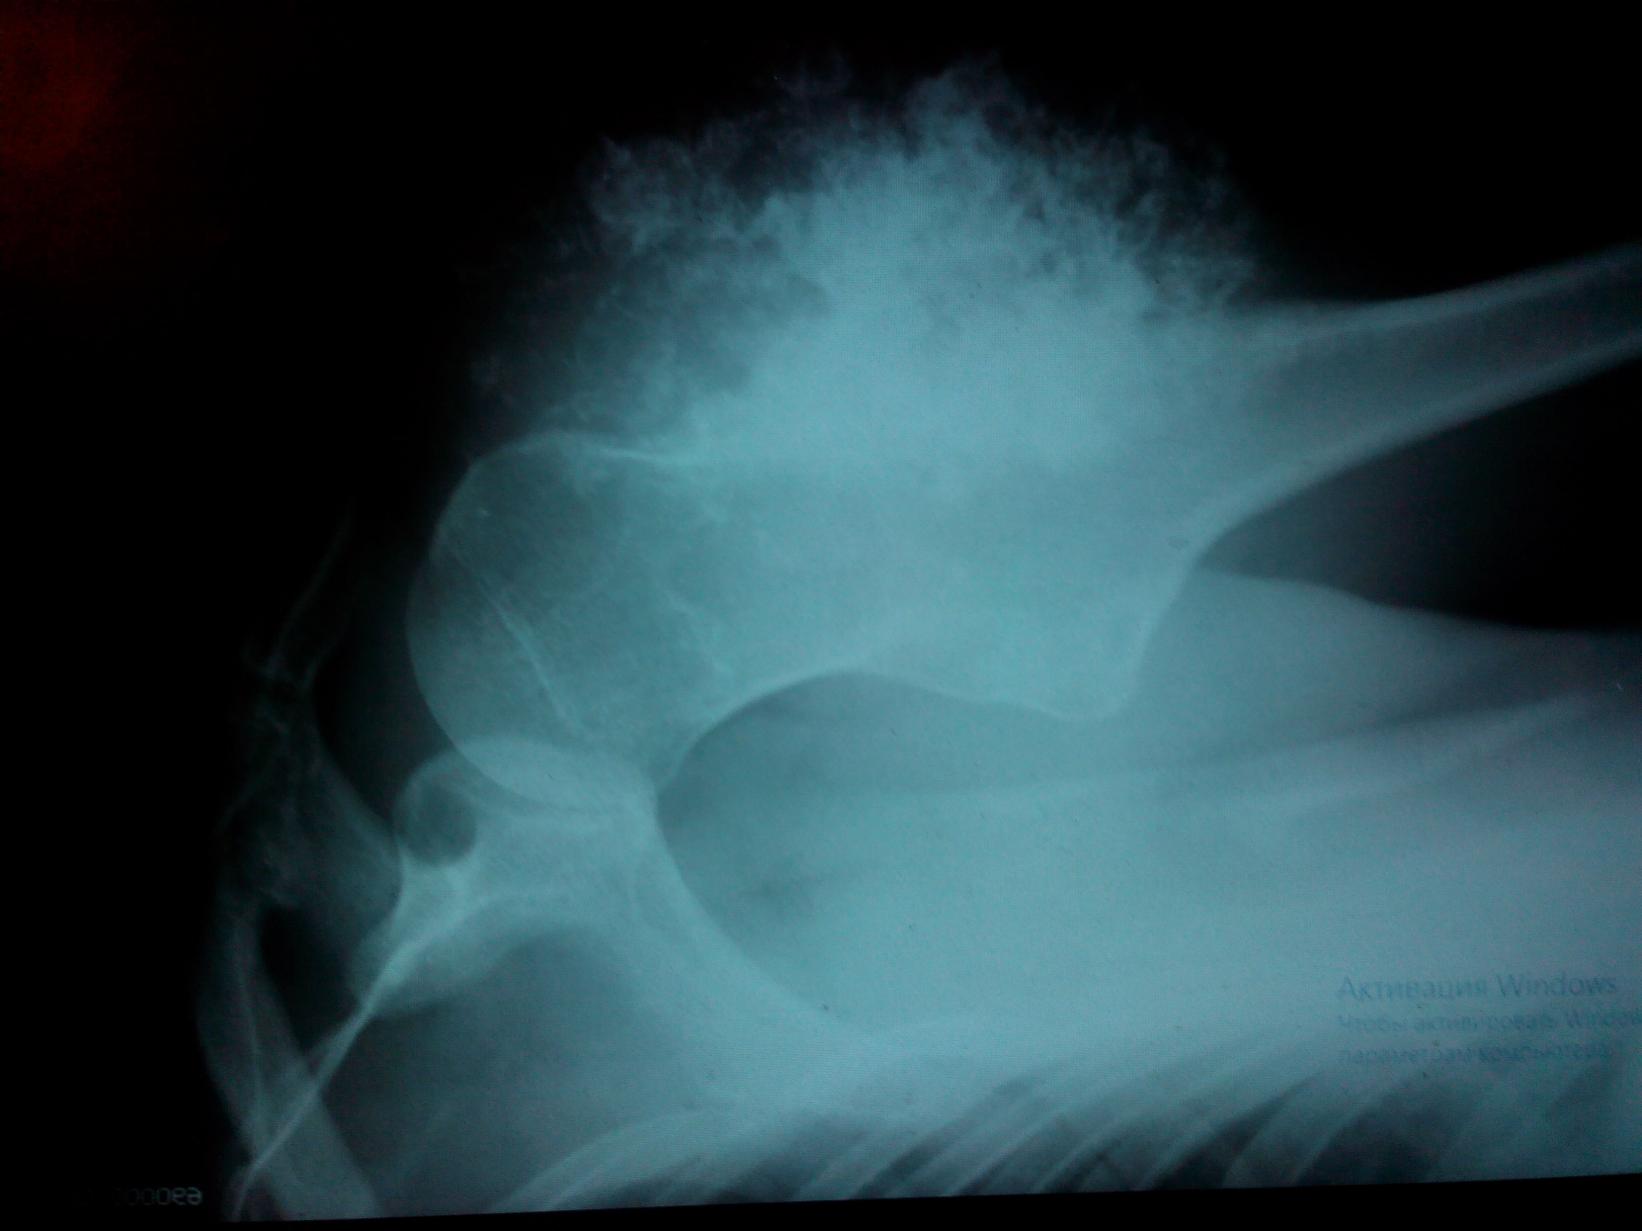

Я 1983 года рождения и после своего тридцатилетия летом 2013 года я заметил на фотографиях что моё левое плечо видоизменилось - стало в окружности больше. По началу я не придал должного внимания и это была моя первая ошибка. Пол года опухоль себя не проявляла в размерах не менялась, но ближе к 2014 года опухоль стала быстро расти. Тут я понял что пора к врачам. Так как наша бюрократия требовала регистрацию я стал оформлять временную регистрацию. Тут я сделал вторую ошибку так как регистрация не требуется потому что медицинский полис привязывается к поликлинике по месту проживания , а не по местурегистрации. Пока оформлял прописку прошло три недели. В начале Февраля 2014 года я обратился в Спб, в Городскую поликлинику №99 и записался на прием к хирургу. Обратился в начале февраля , а номерок на конец февраля. Это была моя третья ошибка - мне надо было попасть на прием к терапевту и это было бы быстрее. На момент когда я пришел к хирургу на прием рост опухоли достиг 10 сантиметров в диаметре. Хирург дал направление на рентген. Рентген кабинет был уже закрыт, снимок сделали только на следующий день. Когда я увидел рентген снимок то я понял что я встрял, только ещё не знал как я встрял. С рентген снимком снова на приём к хирургу и он мне дал направление в СПб ГБУЗ Городская поликлиника № 104

деньги на ветер. Даже далекий человек от медицины поймет что моём случае гистологическое заключение можноподтвердить или опровергнуть без магнитно-резонансной томографии. Мне нужен был диагноз и мне пришлось делать МРТ с подсветкой и обошлось это в 7 000 рублей на 2015 год когда в Спб в частных клиниках цены на аналогичную процедуру были с среднем около 5 000 рублей. После МРТ мне дали заключение и гистолог Алексеева Л.Н. дала патологоанатомическое заключение: хондросаркома G-1. 9220/1. от 03.07.2015